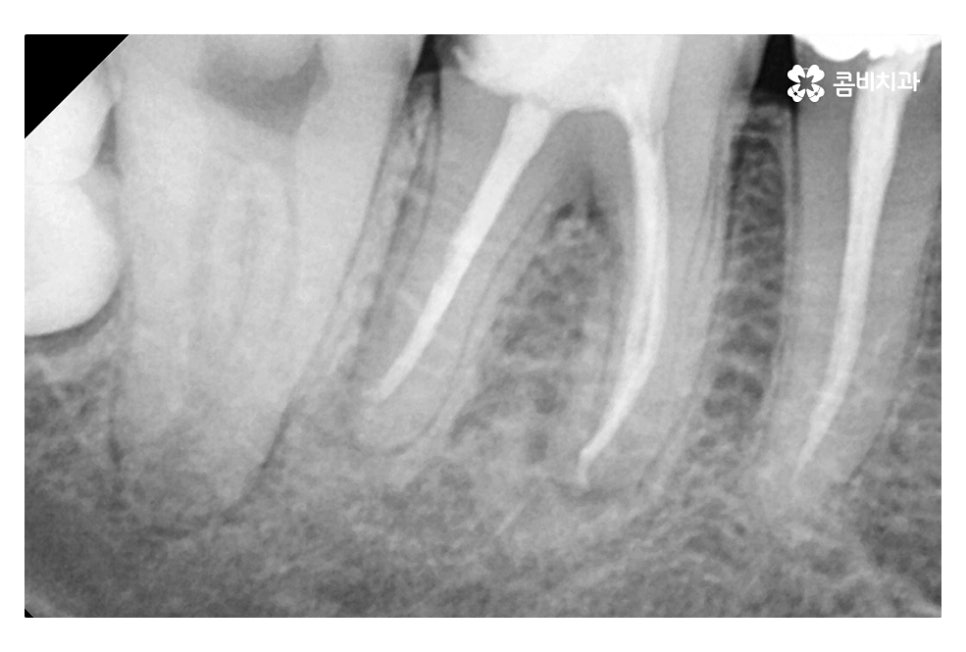

위 사진은 신경을 제거한 후 치과용 재료(GP cone)로 채워 넣은 상태인데

신경치료 후 크라운 치료를 하는 과정은

치아의 신경관을 찾아 미세한 신경 조직을 깨끗하게 제거해야 하며

자연치아를 살리는 중요한 단계라고 볼 수 있어요.